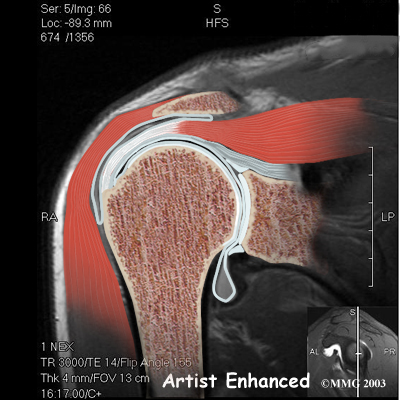

The rotator cuff connects the humerus to the scapula. The rotator cuff is formed by the tendons of four muscles: the supraspinatus, infraspinatus, teres minor, and subscapularis.

Tendons attach muscles to bones. Muscles move the bones by pulling on the tendons. The rotator cuff helps raise and rotate the arm.

As the arm is raised, the rotator cuff also keeps the humerus tightly in the socket of the scapula, the glenoid. The upper part of the scapula that makes up the roof of the shoulder is called the acromion.

A bursa is located between the acromion and the rotator cuff tendons. A bursa is a lubricated sac of tissue that cuts down on the friction between two moving parts. Bursae are located all over the body where tissues must rub against each other. In this case, the bursa protects the acromion and the rotator cuff from grinding against each other.